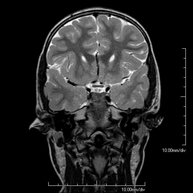

- RM Cerebral (craneal)

Prueba diagnóstica no invasiva que consiste en la obtención de imágenes de alta definición anatómica del cerebro mediante el empleo de un campo electromagnético y ondas de radio (con un emisor y un receptor). No utiliza radiación ionizante. Indicaciones: problemas vasculares, pérdida de memoria, epilepsia, cefalea, malformaciones, sospecha de tumor, meningitis. - RM Cais